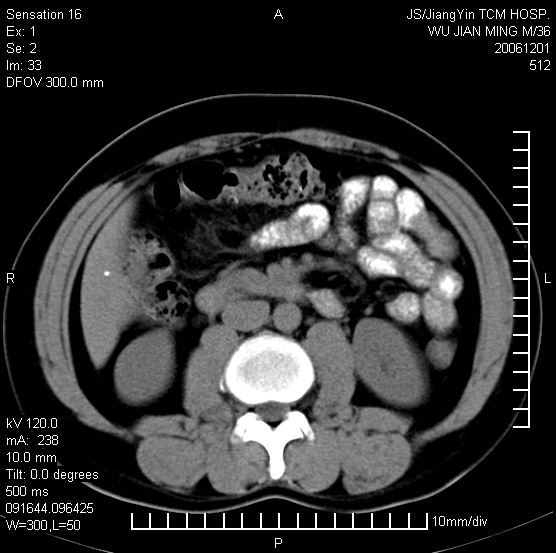

以下是引用dyqct在2006-12-1 21:17:00的发言:[br]左心缘旁及后肋膈窦区见巨大椭圆形混杂密度肿块,周围见大小不等斑片状钙化,内部无强化,周围包膜轻度强化,心脏明显受压变形,即明显占位效应,肿块广基与心包、膈相连。肝、脾内、肝门见多数小结节状钙化影。[br]考虑:1、左心缘旁及后肋膈窦区慢性包裹性胸膜炎(结核性);[br] 2、肝、脾及肝门淋巴结核已钙化。[br]

以下是引用zyx168在2006-12-2 10:10:00的发言:[br][br]肝脾肺内多发钙化灶